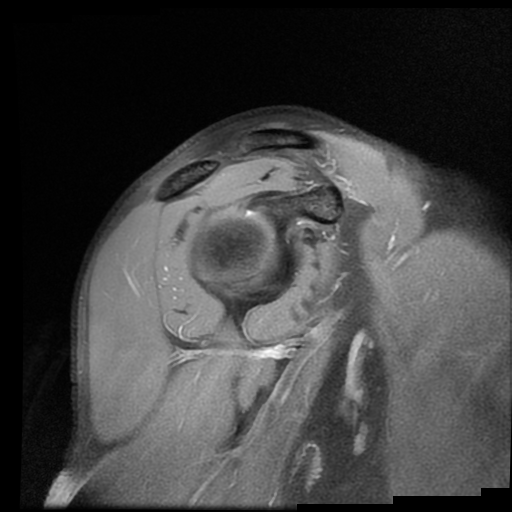

HALLAZGOS IMAGENOLOGICOS

Lesión post traumática de Hill Sachs a nivel de la cabeza humeral, tendinosis aguda del supra espinoso.

El adecuado reconocimiento de esta entidad depende de una evaluación imagenológica precisa. La radiografía puede sugerirla, pero la tomografía computarizada cuantifica con mayor exactitud el volumen óseo comprometido y su relación con la glenoides; por su parte, la resonancia magnética permite valorar además las lesiones asociadas de partes blandas, como el desgarro de Bankart, y estimar el riesgo de “enganche” (engaging lesión) durante los movimientos de abducción y rotación externa. Este documento busca ofrecer una síntesis clara y práctica de la lesión de Hill-Sachs: su fisiopatología, criterios de medición, implicaciones clínicas y opciones de tratamiento, con especial énfasis en la correlación imagenológica que guía la toma de decisiones en el contexto de la inestabilidad anterior del hombro.

Accurate recognition of this entity depends on precise imaging evaluation. Plain radiography may suggest it, but computed tomography quantifies more accurately the volume of bone loss and its relationship to the glenoid, while magnetic resonance imaging also evaluates associated soft-tissue injuries, such as a Bankart tear, and estimates the risk of engagement during abduction and external rotation. This document aims to offer a clear, practical synthesis of the Hill–Sachs lesion: its pathophysiology, measurement criteria, clinical implications, and treatment options, with particular emphasis on imaging correlation to guide decision-making in the context of anterior shoulder instability.

La lesión de Hill-Sachs es un defecto de impactación en la región posterosuperolateral de la cabeza humeral, secundario a luxación o subluxación anterior del hombro. Se produce cuando la cabeza humeral, desplazada anteroinferiormente, colisiona y se “muerde” contra el borde anteroinferior de la glenoides.